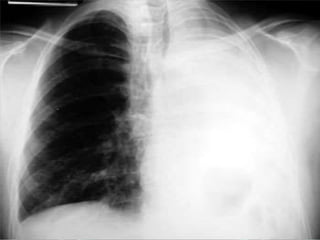

Pneumotórax

• Hipertransparência

(presença de ar no

espaço pleural);

• A pleura visceral

delimita o pneumotórax;

• Não haverá trama

vascular na área;

• Mediastino direcionado

para o lado oposto.

Pneumotórax • Hipertransparência (presença dear no espaço pleural); • A pleura visceral delimita o pneumotórax; • Não haverá trama vascular na área; • Mediastino direcionado para o lado oposto.